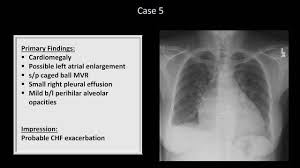

Interpretation of the chest x ray. Chest x ray is probably the most common imaging test. In addition to text and pictures, this tutorial contains interactive features which supplement the text and make it a more dynamic learning. Examination of the chest x ray is a process which requires a systematic approach. Standard frontal chest radiograph (roentgenogram) — upright; Recognizing normal anatomy on the cxr is key to understanding and interpreting abnormalities. Few providers (including mds) are comfortable interpreting their own films. In fact every radiologst should be an expert in chest film reading. Normal heart size is half of the chest width. Generally speaking, a normal cxr should have the lungs looking like zebras in that they are all black with strips. The aim of this study was to investigate the diagnostic accuracy of cxr interpretation by reporting radiographers (technologists). The chest radiograph remains the most important method of chest imaging, providing an easily accessible, inexpensive, quick, and effective diagnostic tool. Learn about chest x ray interpretation with free interactive flashcards.

Normal heart size is half of the chest width. Standard frontal chest radiograph (roentgenogram) — upright; In fact every radiologst should be an expert in chest film reading. Generally speaking, a normal cxr should have the lungs looking like zebras in that they are all black with strips. These images were saved with anonymous biodata for iom radiology collection and teaching purposes.

Chest x ray is probably the most common imaging test. Standard frontal chest radiograph (roentgenogram) — upright; The aim of this study was to investigate the diagnostic accuracy of cxr interpretation by reporting radiographers (technologists). Normal heart size is half of the chest width. Generally speaking, a normal cxr should have the lungs looking like zebras in that they are all black with strips. A collection of data interpretation guides to help you learn how to interpret various laboratory and radiology investigations. It would be wrong to base a diagnosis on only the most obvious features of any chest x ray. In fact every radiologst should be an expert in chest film reading.

Normal heart size is half of the chest width. Few providers (including mds) are comfortable interpreting their own films. © 2005 adam guttentag, md. Chest x ray basic interpretation by vikram patil 37831 views. Generally speaking, a normal cxr should have the lungs looking like zebras in that they are all black with strips. The aim of this study was to investigate the diagnostic accuracy of cxr interpretation by reporting radiographers (technologists). Dr andrew dixon ◉ and dr jeremy jones ◉ et al. Recognizing normal anatomy on the cxr is key to understanding and interpreting abnormalities. It would be wrong to base a diagnosis on only the most obvious features of any chest x ray. Chest x ray is probably the most common imaging test. These images were saved with anonymous biodata for iom radiology collection and teaching purposes. Interpretation of the chest x ray. In addition to text and pictures, this tutorial contains interactive features which supplement the text and make it a more dynamic learning.